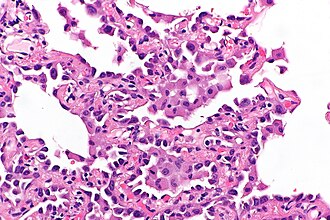

Micronodule of pneumocyte hyperplasia in multifocal micronodular pneumocyte hyperplasia associated with tuberous sclerosis. H&E stain. | |

Features:

- Macrophages within the air spaces.

- Enlarged alveolar lining cells with:

- Hobnail morphology - free (luminal) surface area > attached/basal surface area.

- Round or oval nuclei.

DDx:

- Atypical adenomatous hyperplasia of the lung - usu. do not have macrophages within the air spaces.